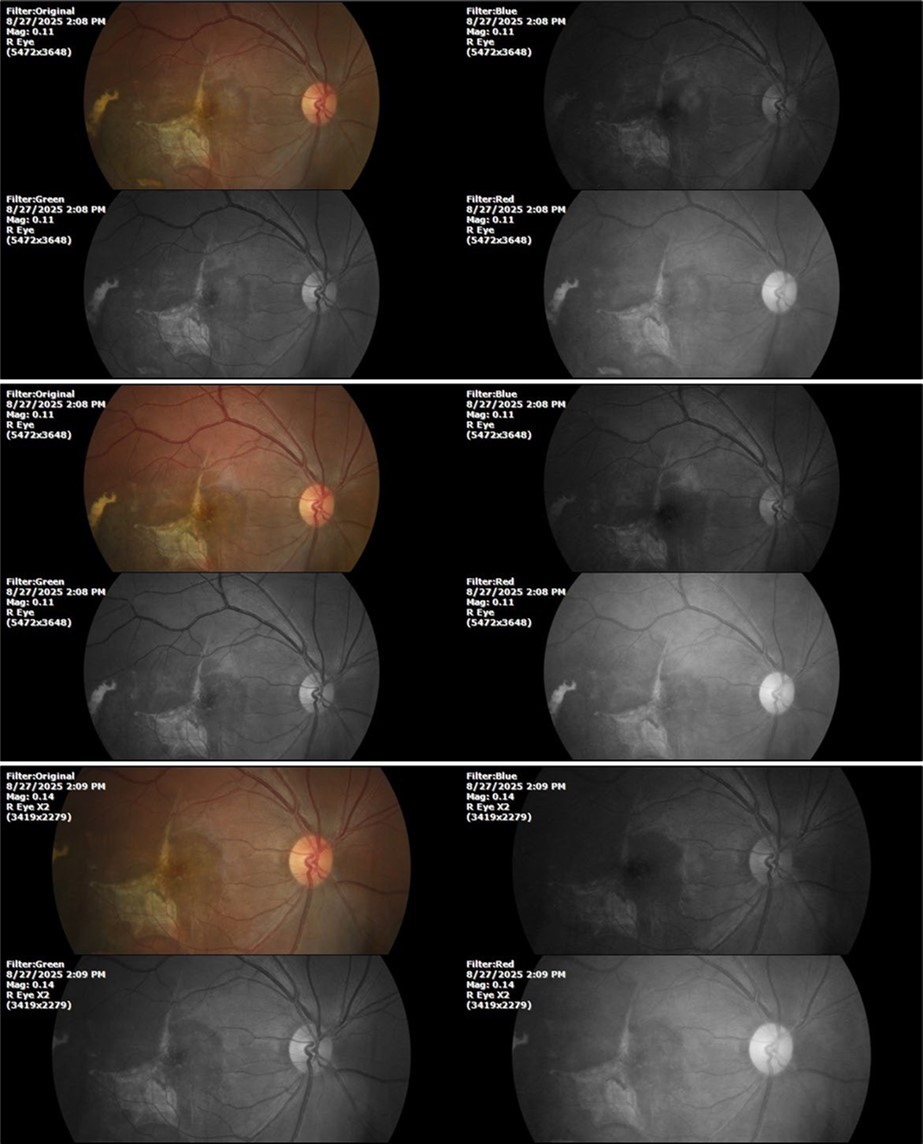

Figure 7.The photograph of the fundus of the right eye shows significant subretinal bleeding, which affects the entire macular area; and some blood is also seen in the vitreous body.

Figure 8.The photograph of the superior temporal region of the retina of the right eye shows the extent of subretinal bleeding as well as retinal edema.

Figure 9.The extent of bleeding, mainly subretinal, is extensive and of significant volume, suggesting choroid rupture in this area.

Figure 10.The location of the bleeding is mainly subretinal, although blood is seen in minimal quantity in the vitreous body.

Figure 17.The photographs show a whitish mass in the place occupied by the blood, which is compatible with the term "ghost cells" used to refer to the accumulations of cell membranes of empty erythrocytes. Bleeding has not increased anymore.

Figure 22.The whitish mass of phantom cells continues to decrease. The treatment continues to be based on ǪIAPI 1®, sublingual drops, three drops every hour, for as long as the patient is awake.

Figure 27.The three previous photographs of the right fundus show that the whitish mass composed mainly of phantom cells continues to decrease.

It's been fine, there's only a little veil that prevents it from seeing well completely, although it's very transparent (Figure 31, Figure 32, Figure 33, Figure 34, Figure 35, Figure 36).

Figure 33.The 3 previous photographs show that whitish mass has almost completely disappeared, and to date only a remnant remains on the left side of the photograph. The chorioretinal scar that is now observed corresponds to the area affected by the blunt trauma, which presumably caused rupture of Bruch's membrane. Fortunately, the macular region has recovered almost in its entirety, so the impairment in central vision was minimal.

Despite being a patient affected in the macular region by the blunt trauma he suffered at work, the recovery was very satisfactory, which is not easy to achieve with established orthodox treatments, including surgery and powerful anti- inflammatories.